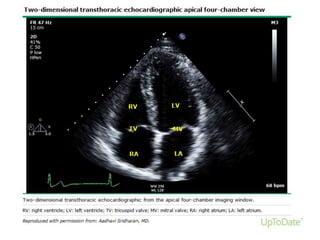

Apical 4 chamber view

• Transducer at

apex

• Visualize all 4

chambers

Apical 4 chamberview • Transducer at apex • Visualize all 4 chambers